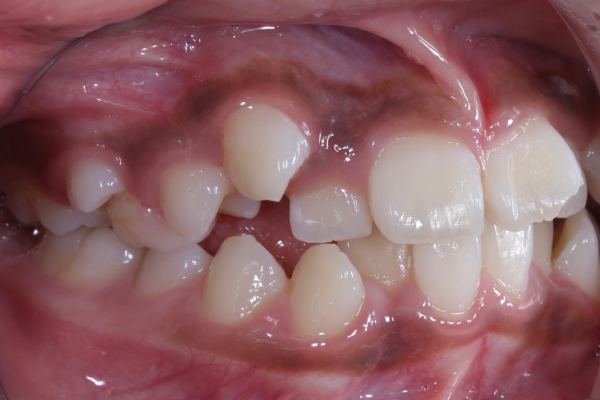

BEFORE

患者様は10代の女性で、前歯を中心とした歯並びのガタつき(叢生)を気にされて来院されました。できるだけ抜歯をせずに矯正治療を行いたいというご希望があり、精密検査を実施しました。

精密検査では、前歯部を中心とした叢生(歯の重なり)が確認され、現在だけでなく将来的な口腔環境も考慮した治療方針について詳しくご説明した上で、矯正治療を開始することとなりました。